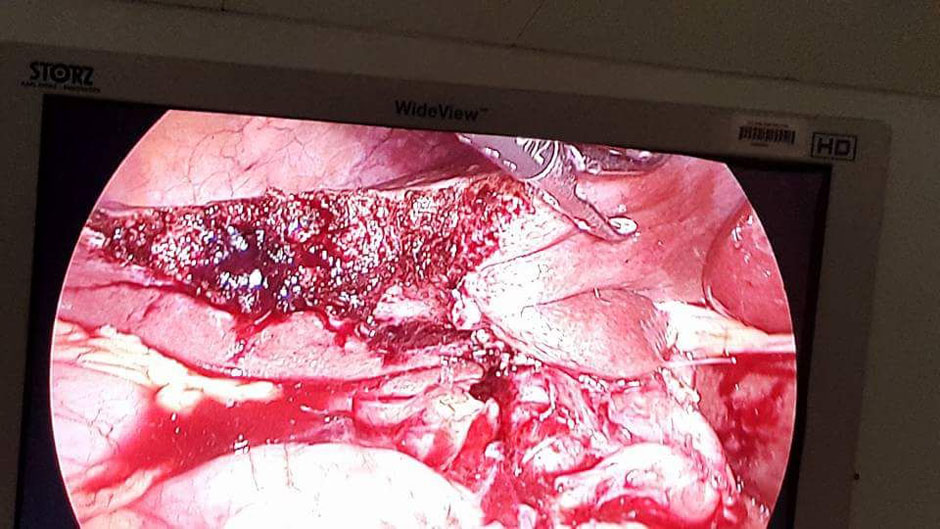

A Young lady who was a small kid...when her mother was operated for a Complex Gastrointestinal condition almost 14 years back by Dr Suddhasattwa Sen suddenly came in with severe blood loss from Gastrointestinal tract with a loss of almost 2 to 3 litres of blood with Shock with fainting . Further stabilisation was done and then extensive investigation revealed not only Piles and GI Ulcers but also SRUS Bleeding ulcers in rectum. A condition called Solitary Rectal Ulcer Syndrome ( a complex and difficult to cure anorectal problem ) . Her hemoglobin dropped to below 7 gm% She finally underwent surgery after 5 days and left home after 2 days post op without any further bleed or problems .